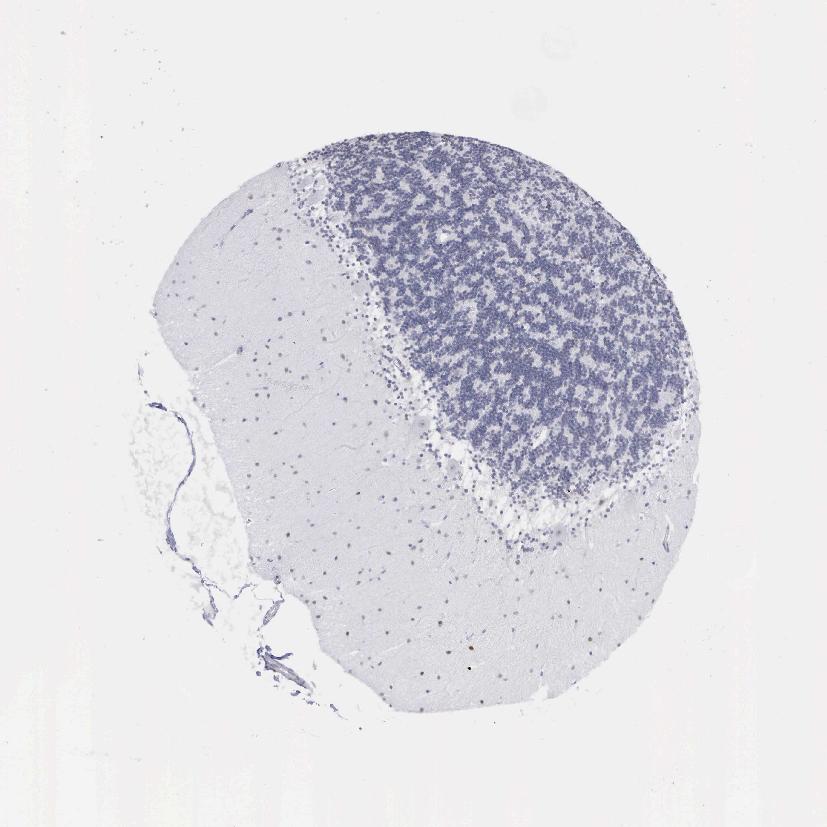

CEREBELLUM - Antibody stainingi

Antibody staining in the annotated cell types in the current human tissue is reported as not detected, low, medium, or high, based on conventional immunohistochemistry profiling in selected tissues. This score is based on the combination of the staining intensity and fraction of stained cells.

Each image is clickable and will lead to virtual microscopy that enables deeper exploration of all samples and also displays staining intensity scores, fraction scores and subcellular localization as well as patient and tissue information for each sample.

Antibody HPA000727

Purkinje cells Low

Cells in granular layer Not detected

Cells in molecular layer Not detected